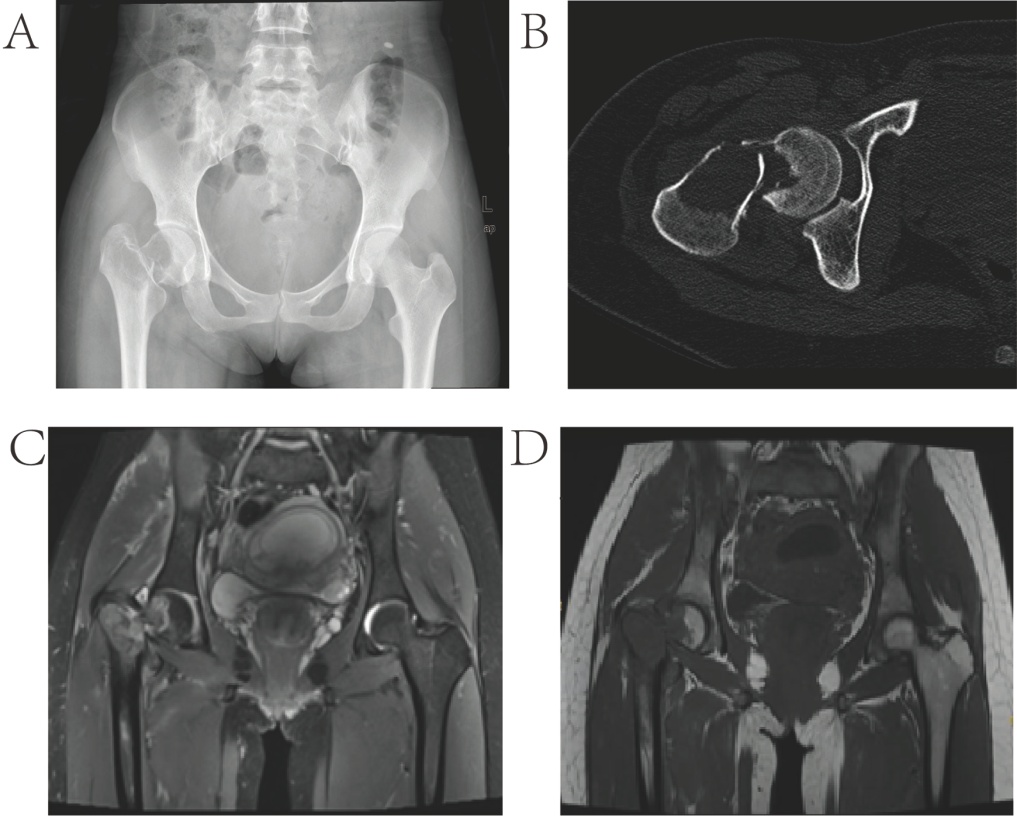

入院后,完成了一系列影像学检查(见图1(A)~(D))。右髋关节对比增强磁共振成像显示股骨颈有一个囊性病变,伴有病理性骨折。病变显示边缘光滑、边界清楚、周边有对比增强但无浸润性改变。影像学发现与肉芽组织增生和修复反应相关的表现,表明在肿瘤早期进展过程中存在微骨折愈合稳态。这种平衡可能被低能量创伤打破,从而导致患者出现临床表现。经过多学科讨论,考虑诊断为妊娠9周合并右股骨颈关节外病理性骨折,需要紧急骨科处理和终止妊娠。主要的手术挑战如下:1) 尽管病变范围大,但缺乏确诊的组织病理学诊断;2) 需要在妊娠早期对病理性骨折进行时效性管理;3) 广泛刮除术导致股骨头缺血性坏死的风险与不完整切除导致的潜在复发风险。考虑到患者年轻,首选方法是病灶刮除加植骨,而全髋关节置换术作为挽救性选择。

(A) 骨盆前后位X线片:右侧股骨头颈交界处存在囊性病变,并伴有病理性骨折线。(B) 轴位CT图像:股骨颈及大转子处皮质变薄,髓腔内可见溶骨性破坏(平均CT值:33亨氏单位)。(C) (D) 髋关节MRI:右侧股骨近端干及颈区可见一不规则病变,T1加权成像(T1WI)呈低信号,T2加权成像(T2WI)呈不均匀的轻度低信号,边界清晰。对比增强成像显示病变边缘呈明显强化。此外,髋关节囊内可见不均匀的T2信号强度,提示存在复杂性积液或出血。

Figure 1. Preoperative imaging examinations of the patients

1. 患者的术前影像学检查